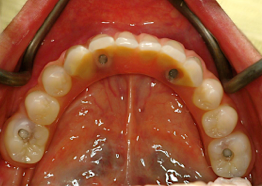

2.歯の形はほぼ天然歯があった時と同じになるので取り外しの義歯に比べて違和感がなく、手入れもインプラントの本数を少なくすることにより、清掃もし易くなっています。

3.インプラントの本数を少なくできることは、経済的も優れています。従来の治療では、無歯はでは10〜14本のインプラントを埋入していたのでそれと比較すると、かなりの治療費を削減できると考えます。